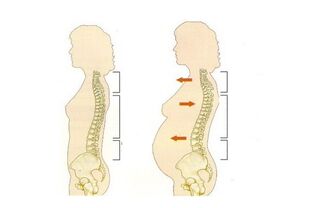

- hamilelik;

Bu durumların her birinde ağrı farklı bir doğada olabilir. Acil nedene bağlı olarak, kadın vücudunun özellikleri, hamilelik sırasında beldeki stresin derecesi, kadının yaşı, işi, mesleki faaliyet türü, ağrı farklı şekillerde kendini gösterebilir.

- Daha önce de belirtildiği gibi, hamilelik ve doğum da bel ağrısı olasılığını artırır;